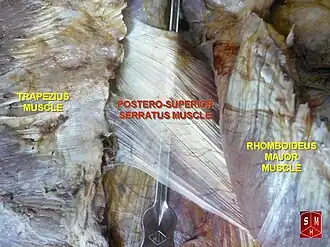

Serratus posterior superior muscle

Thin film-like object, at center, is serratus posterior superior muscle. | |

The serratus posterior superior muscle is a thin, quadrilateral muscle. It is situated at the upper back part of the thorax, deep to the rhomboid muscles.

Structure

The serratus posterior superior muscle arises by an aponeurosis from the lower part of the nuchal ligament, from the spinous processes of C7, T1, T2, and sometimes T3, and from the supraspinal ligament.[2] It is inserted, by four fleshy digitations into the upper borders of the second, third, fourth, and fifth ribs past the angle of the rib.[2]